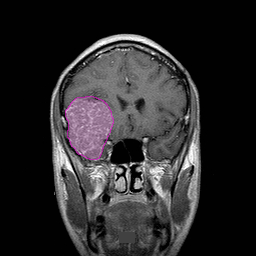

Τα μηνιγγιώματα του εγκεφάλου είναι οι πιο συχνά διαγνωσκόμενοι πρωτοπαθείς όγκοι της κρανιακής κοιλότητας. Εκφύονται από τις μήνιγγες, τα ινώδη περιβλήματα, του εγκεφάλου και είναι, στο μεγαλύτερο ποσοστό τους, καλοήθεις με αργή ανάπτυξη. Ανάλογα με τη θέση και το μέγεθος τους μπορεί να προκαλέσουν διάφορα συμπτώματα όπως επιληπτικές κρίσεις, αδυναμία ή/και υπαισθησία (μούδιασμα) σε ένα ή περισσότερα άκρα, διαταραχές του λόγου ή της όρασης, κ.α. Όχι σπάνια ανακαλύπτονται τυχαία σε απεικονιστικούς ελέγχους μη έχοντας προλάβει να δημιουργήσουν συμπτώματα. Η θεραπεία τους, όταν προκαλούν ή ενδέχεται να προκαλέσουν συμπτώματα είναι χειρουργική, ακτινοχειρουργική ή, σπανιότερα, ακτινοθεραπευτική. |

Διάγνωση Απαραίτητα είναι: Η λεπτομερής λήψη ιστορικού και η κλινική εξέταση, Η μαγνητική τομογραφία του εγκεφάλου με σκιαγραφικό, Σε ορισμένες περιπτώσεις: Η μαγνητική αγγειογραφία ή/και φλεβογραφία του εγκεφάλου, Η μαγνητική τομογραφία του εγκεφάλου με σκιαγραφικό για νευροπλοήγηση, Ηλεκτροεγκεφαλογράφημα και άλλες εξειδικευμένες εξετάσεις όπως μέτρηση οπτικής οξύτητας και οπτικών πεδίων προτείνονται κατά περίπτωση. |